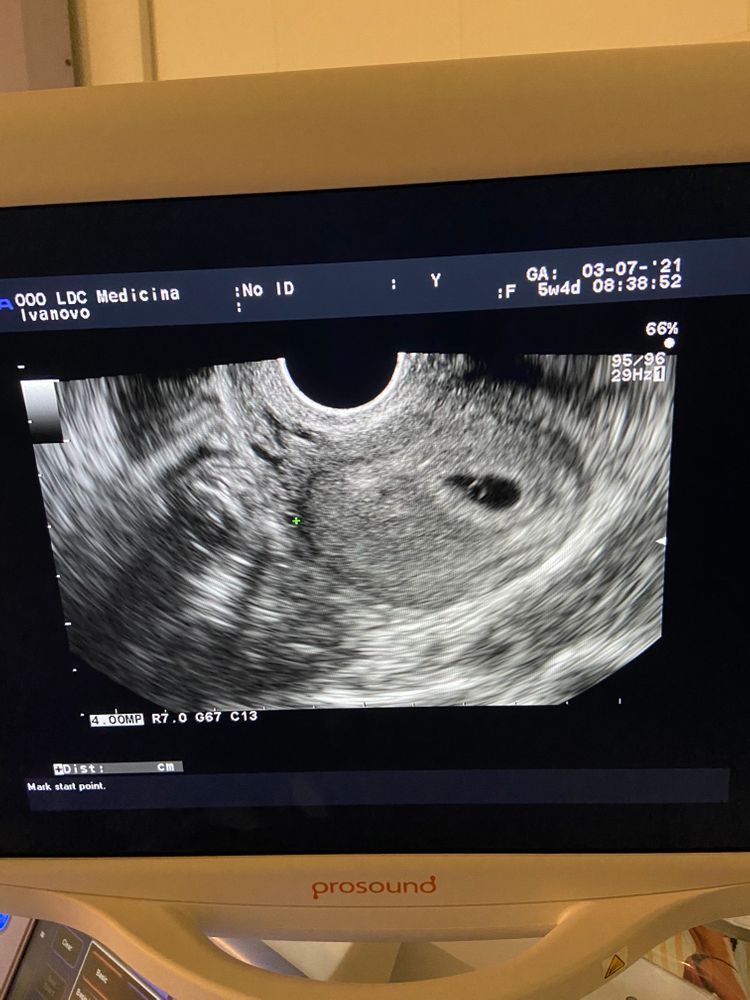

Сходила к другому специалисту

Ну, что я Вам вчера написала про Вашу опытную узистку с сорокалетним стажем и виденьем мутной жидкости в ПЯ?

Елена, это вообще шок! Женщина в клинике эко работает. Это ещё не все ее перлы: 1) идите к гинекологу за гормональной поддержкой, леченые беременности лучше, чем нелеченые 2) ну про ХГЧ я уже говорила, как она высказалась 3) ну да, погуляйте ещё, это же у экошников все по книжке, а у вас сб в 5 недель может ещё и не быть, хотя должно уже короче, желания идти во второй раз к ней нет😢

У меня (думаю, и у всех) такое же было. Оно так и должно выглядеть😊 Да, через пару недель уже с/б послушаете. Поздравляю! Пусть всё будет хорошо и дальше!

Вот , а вы переживали ) заодно и нашли хорошего узиста😉 на ваши сроки все у вас хорошо, а гипертонус ну не без его 😅пейте магний и отдыхайте

Прям картинка из учебника почти 👍 из головы всё выкидывайте, отдыхайте и прям кайфуйте от жизни. Всё прекрасно 🌸